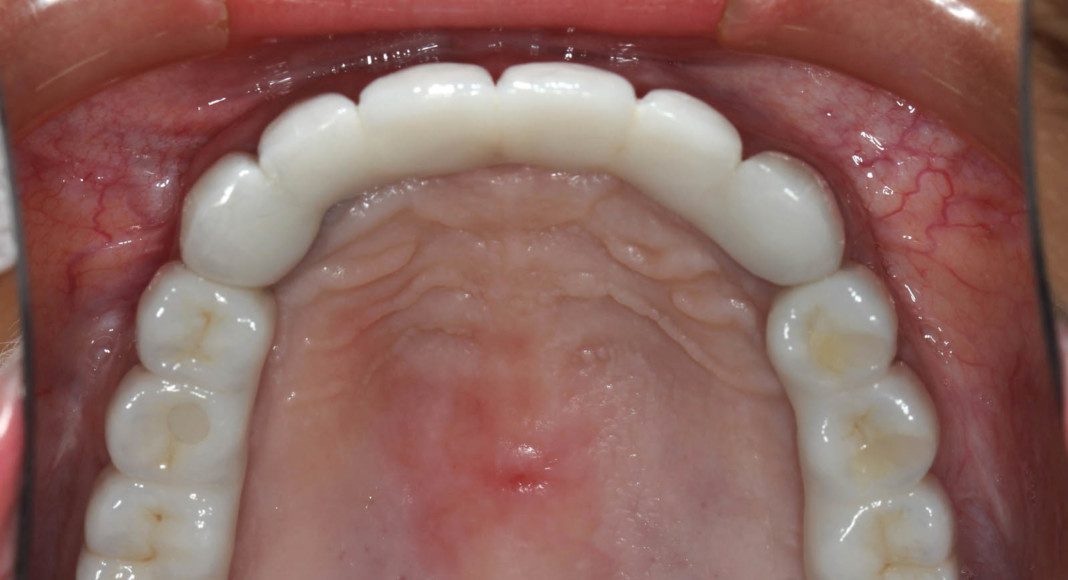

Lower zirconia bridge, off the master cast. This is the intaglio (tissue side) of the prosthesis. Note that is flat to convex for easy cleaning.